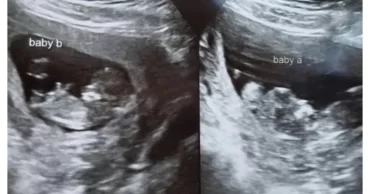

Double Trouble on the Horizon